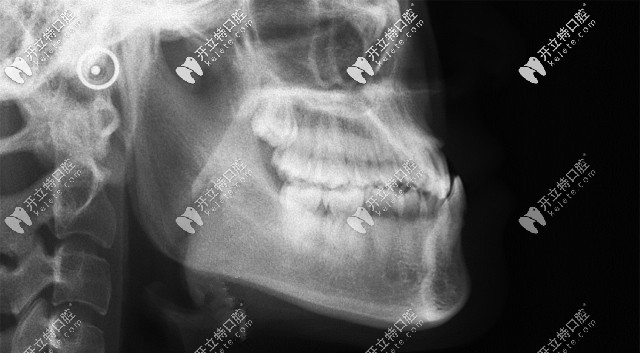

骨性地包天矯正

從這張頭顱側(cè)位片,可以清晰的看到顧客牙齒情況是骨性反頜(地包天)▲